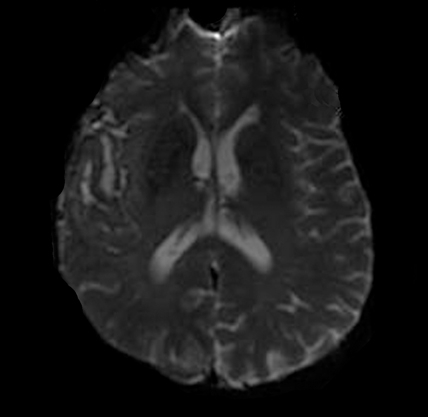

Diffusion Weighted MRI (DWI)

Diffusion Weighted MRI (DWI) shows alterations in tissue integrity— the ability of body tissues to regenerate and/or repair to maintain normal physiological processes. In ischemic injury—such as many types of stroke or when blood is not able to get to all parts of the brain—there is a chemical reaction in the cells. As the cells die because of lack of blood flow (with oxygen), there is an increase in sodium and this changes (increases) the amount of water in the tissue. DWI is very sensitive to this change. In fact, using DWI, doctors can identify a stroke or ischemic injury within seconds of occurrence.